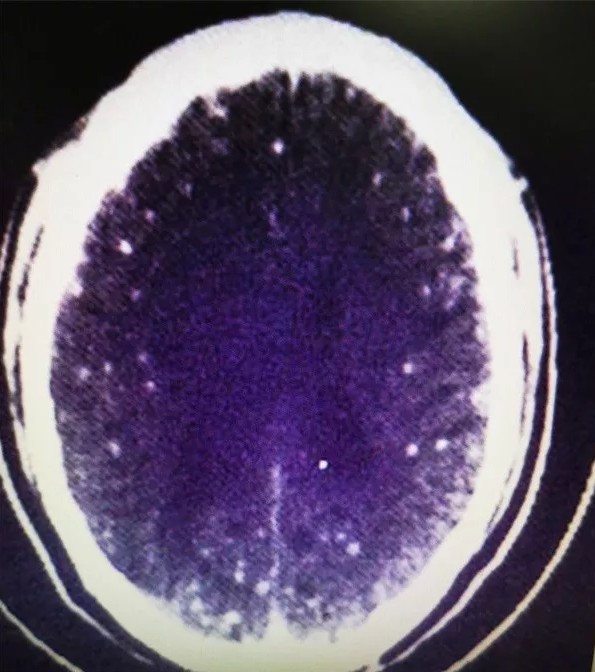

Se você é fã de carne de porco, o caso do chinês Zhu Zhongfa talvez torne você ainda mais exigente quando o assunto é o bom preparo desse alimento. Isso porque mais de 700 ovos de tênia foram encontrados no cérebro do homem, após ele ingerir um caldo com carne mal cozida.

Como o cérebro humano é muito vascularizado, os animais costumam se instalar por lá. Ainda assim, outras regiões também estão em risco: o próprio Zhu apresentou infestação nos pulmões.